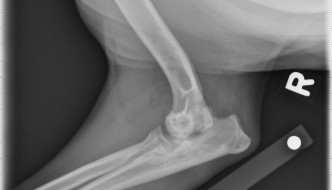

Today's case is a 1-year-old mixed breed dog with right thoracic limb lameness. What are your findings? … [Read more...]